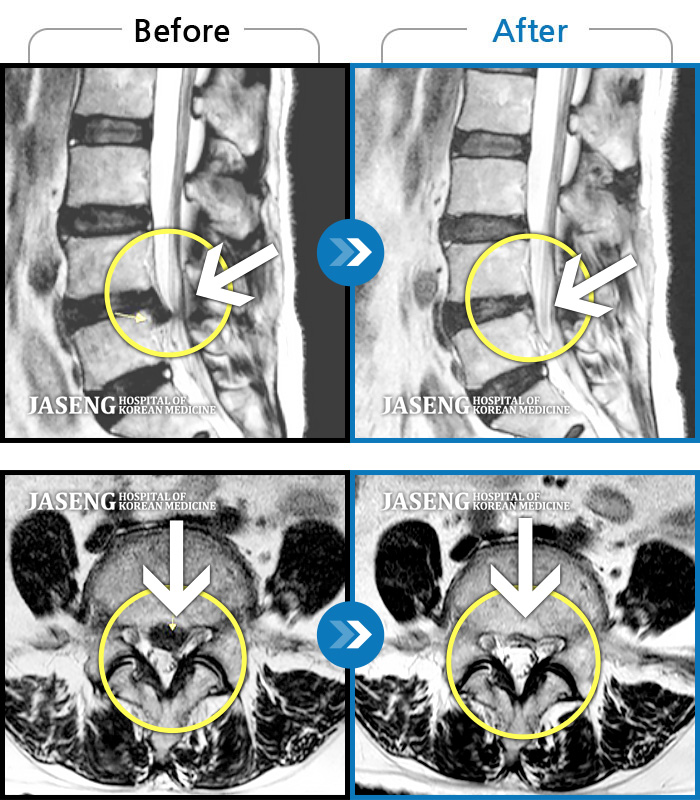

MRI 치료사례

허리통증, 왼쪽 다리 저림 및 통증